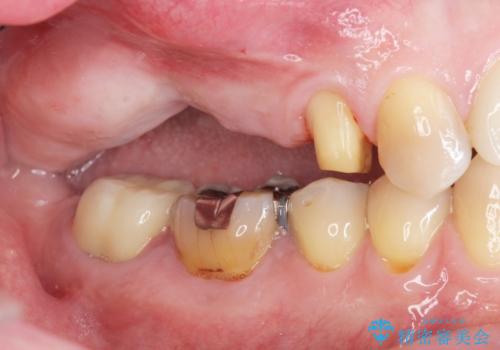

- 破折した歯を放置し、骨が高度に吸収した状態でインプラント治療を希望し来院されました。

インプラントを適切な位置に埋入し仕上げた後にも清掃性を高めるには、必要十分な骨となだらかな歯肉形態の獲得が必要です。

インプラント埋入時に骨の造成を、2次手術時に歯肉の凹みを整え厚みを一定にするような治療を進めていきます。